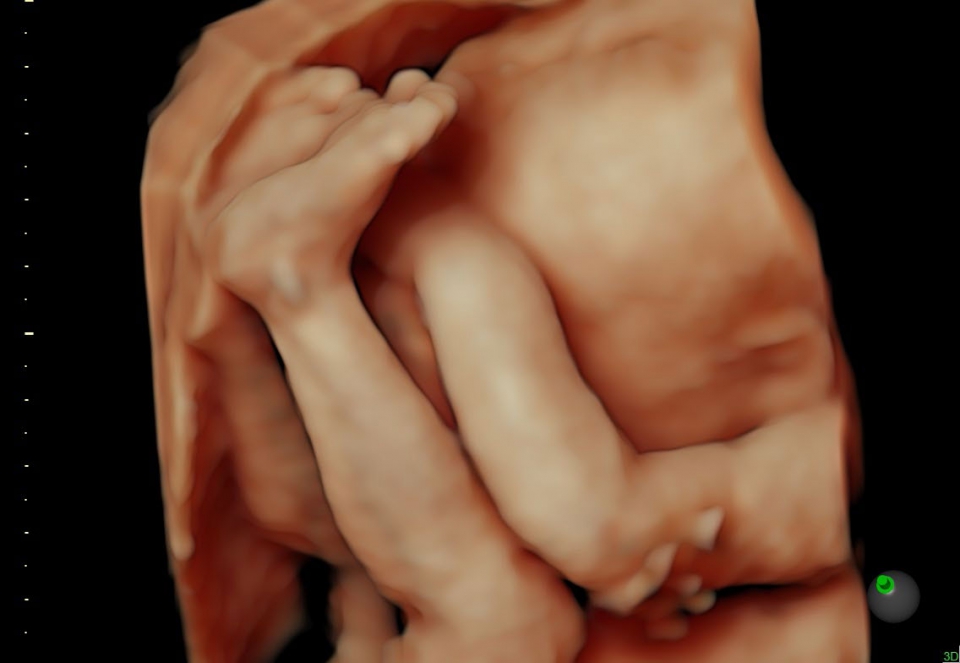

УЗИ аппарат Voluson S10 позволяет проводить обследования высочайшего уровня с максимальной точностью диагностики. Благодаря технологии Voluson Core Architecture достигнут высокий уровень качества изображений с возможностью последующей обработки и анализа даже после проведения скрининга. Технология HDlive делает изображения удивительно реалистичными и объемными.

Основные достоинства системы Voluson S10:

• Качественная диагностика: Благодаря высокотехнологичной платформе и инновационным технологиям, система обеспечивает высокое качество визуализации и быстрое получение объемных изображений, что позволяет врачам устанавливать точные диагнозы.

• HDlive в 3D и 4D - режим перемещаемого виртуального источника освещения - "виртуальная фетоскопия"